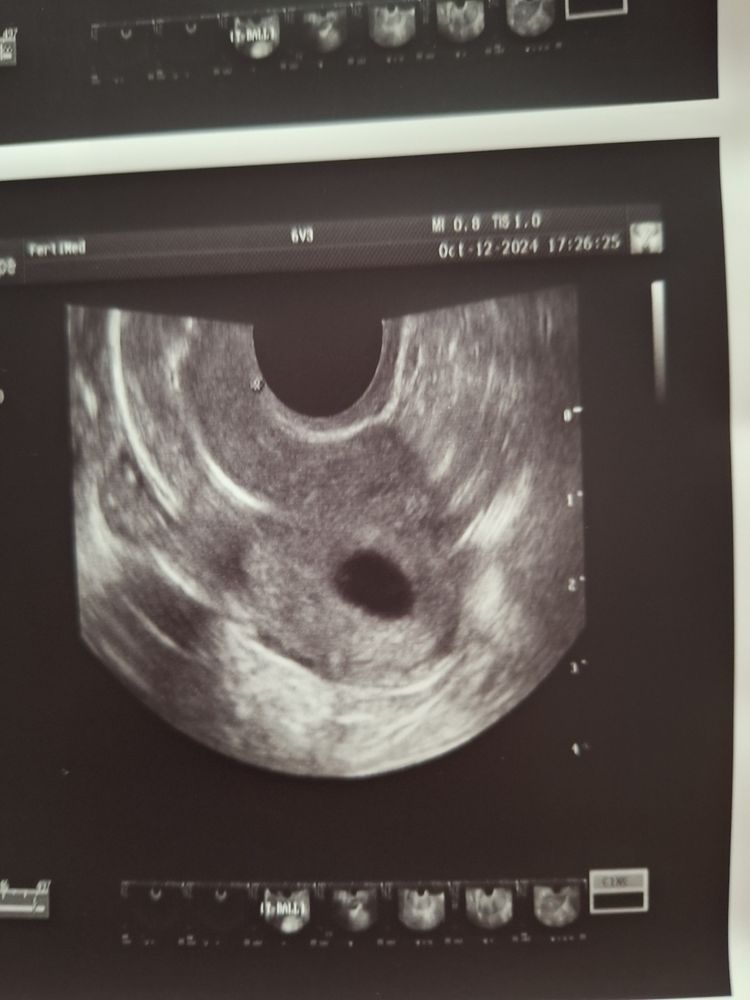

В октябре прошла ГСГ эхо в фертимед , врач прямым текстом сказала- трубы не прлходимы, вообще, жидкость стоит в углах матки и ни на мм в трубы не заходит. Нафоткала узи, дала заключение. С ним я поехала к репродуктологу в МиД, выбирала по отзывам, доктор очень мне понравилась. Она взяла снимки узи и первое что сказала- как не прлходимы? Вот же жидкость, до середины. А дальше либо не сфоткали, либо неизвестно. В общем я в шоке. Я читала и про спазм труб, и что бывают ошибки, но чтоб вот так? Человек который делал гсг и своими глазами смотрел просто не увидел что жидкость проходит? Даже до середины. Все же это совсем не " не прлходит, стоит в матке" Поговорите со мной.